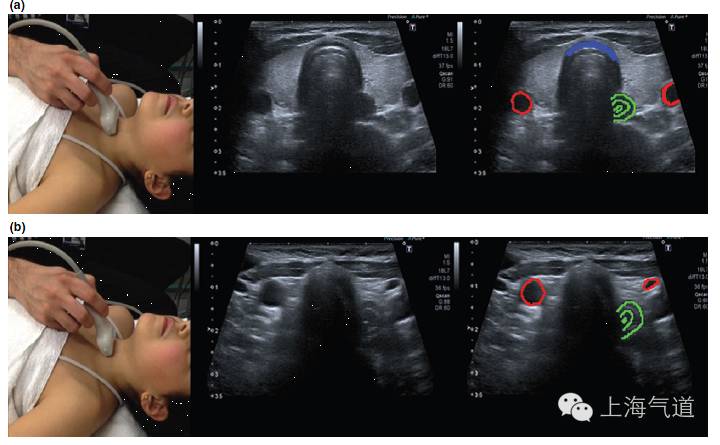

图4a. 假声带水平横截面显示,黄色为带状肌,蓝色为甲状软骨,橙色为假声带。b.将探头轻微向尾端移动至真声带水平,蓝色为甲状软骨,橙色为真声带,红色为前联合,黄色为杓状软骨

图5 a. 将探头继续下移,蓝色为低回声的气管环前壁,绿色为多层环状结构的食道,红色为颈动脉。b. 将探头继续下移,甲状腺影像逐渐消失